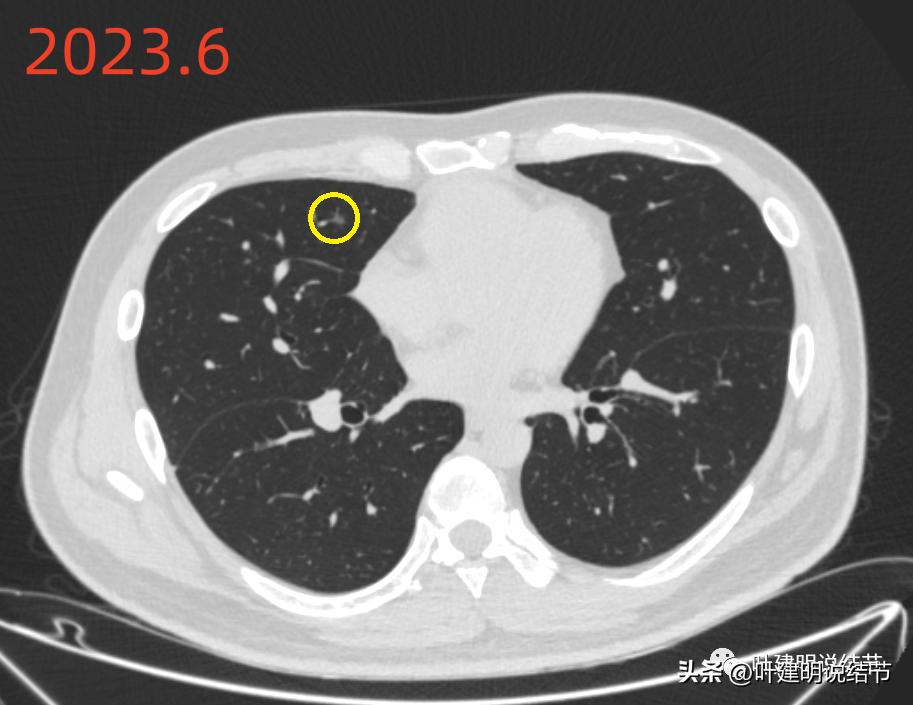

再来看2023年6月的影像情况:

右中叶病灶D较2019年时也没有明显变化,膨胀性不够,但持续存在,考虑慢性炎伴纤维增生或肺泡上皮增生可能性大,能随访。

左下病灶B持续存在,密度略有增高的样子,轮廓清楚,有微小血管征,仍要考虑肿瘤范畴的,以原位癌可能性稍大,大小无明显进展。

绿色圈起来的左上叶微小结节一直有,密度高,轮廓略糊,考虑是良性纤维增生结节;黄色圈起来的右侧的小片状磨玻璃影,非圆形或类圆形,且对比无进展,考虑是少许纤维增生。左下主病灶持续存在,轮廓较为清楚,但实性成分不明显,考虑不典型增生或原位癌可能性较大,目前风险不算高,个人以为仍可随访;左下次病灶密度显高,边缘略糊,不太像恶性。原来又炎症过,对比此前此处刚好是炎症较为明显的位置,所以比较符合慢性炎点,目前风险低,能随访。意见供参考!